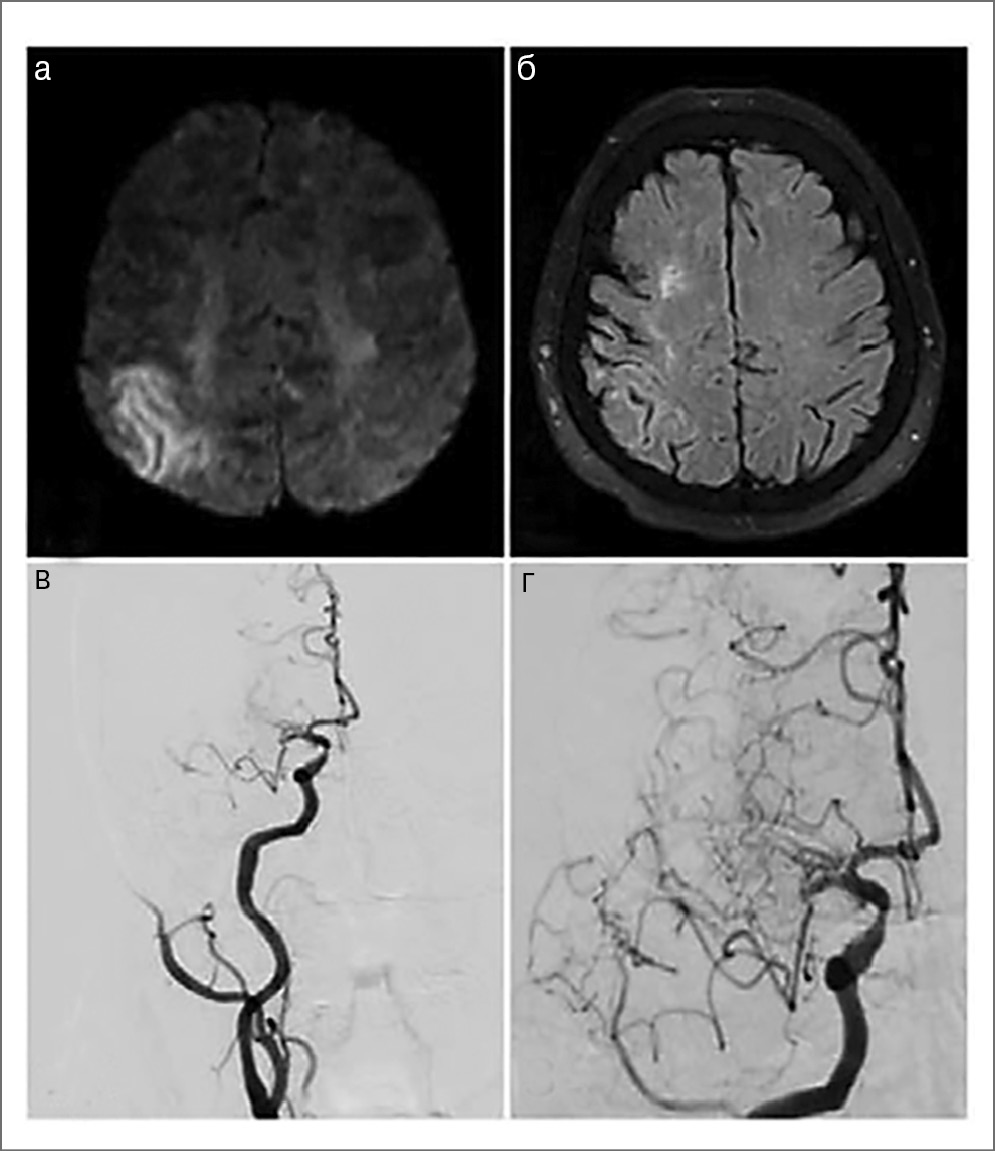

В диагностике лакунарного инсульта ведущее значение имеют МРТ головного мозга с оценкой признаков ЦМА в соответствии с критериями STRIVE [38] и исключение ИКА (рис. 5).

Рис. 5. Клинический пример. Пациент 64 лет, страдающий артериальной гипертензией и сахарным диабетом 2-го типа: а – лакунарный инфаркт в зоне полуовального центра слева (МРТ DWI); б – лакуны в глубинных отделах обоих полушарий, гиперинтенсивность белого вещества (МРТ FLAIR); в – расширение глубинных периваскулярных пространств (T2); г – нормальный результат бесконтрастной МРА. Все это соответствует проявлениям гипертензионной микроангиопатии.